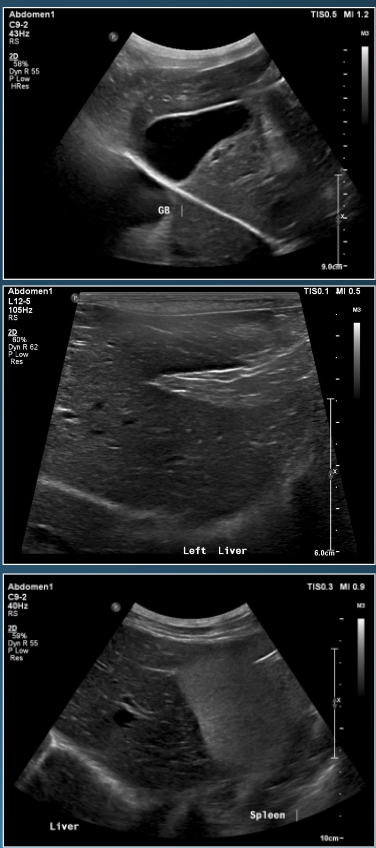

What is shown in these images?

A

normal ultrasound of the liver

How well did you know this?